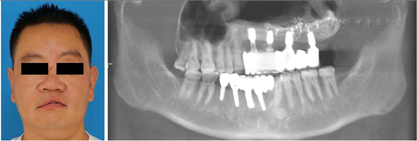

患者伤后17个月复诊,本次主要进行种植术后二期手术并对周围牙龈进行修整(图11)。种植体周围牙龈组织稳定后,上下颌取模制作种植义齿,恢复正常咬合关系,最终于伤后18个月完成所有治疗。

患者治疗历经18个月4次手术,颌面部骨折、骨缺损、软组织创伤畸形和牙缺失均得到了完善的治疗,面部外形及对称性得到了基本的恢复,咬合关系基本正常(图12),目前已经能过够回到正常的生活当中。